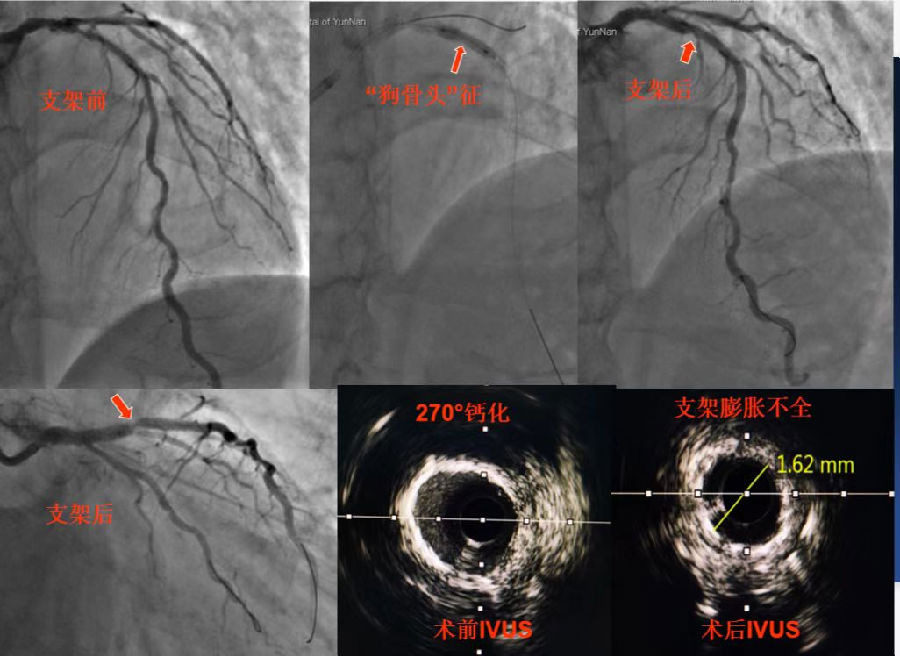

8月1日手术团队再次为患者进行介入治疗,但这次手术并不顺利,术中造影及血管内超声(IVUS)检查均提示:左主干-前降支近中段严重钙化病变,局部钙化达到270°,但考虑患者为支架内再狭窄,使用旋磨技术治疗手术风险高,可能发生严重并发症,故改为应用高压球囊及切割球囊进行充分预扩张处理,于病变处再次植入支架,但新问题接踵而至,术中发现支架植入后使用后扩张球囊反复高压扩张均不能使支架充分膨胀,出现棘手的“狗骨头征”,复查血管内超声显示:再次植入的支架局部膨胀不全,最小管腔面积仅为2.65mm2,且支架外侧仍存在严重钙化环,因手术时间较长,考虑患者安全,遂暂时结束手术。但这样的手术结果远未达到满意的疗效,且有血栓形成威胁患者生命的风险。冠心病中心对此特殊病例高度重视,在北阜专家叶绍东教授、崔成教授和齐峰教授亲自主持下专门针对后续治疗方案进行了充分分析讨论,专家们一致认为可以考虑使用目前最先进的冠脉血管内冲击波球囊来解决患者的这一难题。

经过精心准备,8月12日一早,由叶绍东主任、崔成主任、白洁主任、杨俊主任等组成的专家团队共同为患者实施该项治疗。为保证手术的精准性和安全性,术中使用高分辨率的血管腔内影像学检查——光学相关断层成像(OCT)进行指导。经OCT测量发现患者原支架膨胀不全处管腔面积仅有3.14mm2 ,局部为270°严重钙化,故按照原定计划使用冠脉内冲击波球囊对局部病变共发放80次脉冲充分处理后,再使用高压球囊对病变行充分扩张,复查血管造影清晰显示原病变处管腔狭窄显著减轻,血流通畅,OCT显示局部管腔面积扩大为7.8mm2,支架全程均充分贴壁,膨胀良好,术中患者生命体征平稳,无明显不适症状,手术顺利完成且治疗效果满意。

图6 冲击波球囊治疗前后造影对比

.png)

图7 冲击波球囊治疗前后OCT检查影像